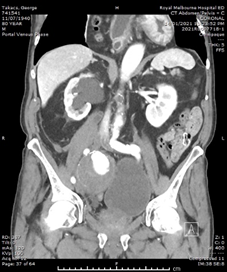

He had normal inflammatory markers, Hb 133g/L and Creatinine 104umol/L. A Computed Tomography (CT) scan of the abdomen and pelvis was performed, with the differentials considered being incarcerated inguinal hernia, diverticulitis or malignancy. However, the CT showed a 75mm, contained ruptured right internal iliac artery (IIA) aneurysm, with no active contrast extravasation (Figure 1). There was perianeurysmal haemorrhage in the right iliac fossa which extended into a small fat-containing inguinal hernia (Figure 2). There was also bladder distension and moderate-to-severe right hydroureteronephrosis secondary to the large aneurysm.

Figure 1 Arterial-phase CT images of the abdomen and pelvis. (A) Axial image showing the right internal iliac artery aneurysm with contained perforation and no contrast extravasation. (B) Coronal image showing the aneurysm exerting mass effect on bladder, and right sided hydronephrosis.